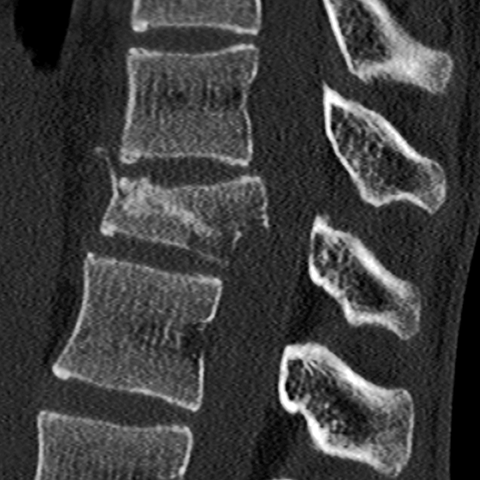

40 year-old man who fell from a tall ladder complains of back pain [1 of 2]